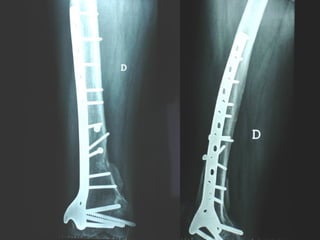

Dal Gennaio 2000 al Febbraio 2006 abbiamo trattato 167 fratture chiuse  con placca percutanea  in 164 pazienti :  27 lesioni diafisarie di gamba, 12 piloni tibiali ,  11 fratture prossimali di tibia, 36 fratture sovracondiloidee di femore, 17 fratture diafisarie di femore, 43 fratture metaepifisarie prossimali di omero, 21 diafisarie d’omero.  156 guarigioni 8 fallimenti

I buoni risultati ottenuti dipendono da 5 punti fondamentali:   una accurata riduzione percutanea della frattura  precise vie di accesso  l’utilizzo della placca che consenta il più lungo braccio di leva possibile il pretensionamento della placca  una sintesi con un ridotto numero di viti

Placche lunghe e pretensionate

Placche lunghe e pretensionate Sintesi con un ridotto numero di viti

Stabilità tramite attrito placca    osso

Osso porotico Stabilità con viti autobloccate

VANTAGGI CHIRURGIA MININVASIVA Mini Open Inserimento della placca sottocutaneo per scivolamento Viti percutanee Preservazione dei tessuti molli Ridotto danno vascolare Rapida ripresa funzionale